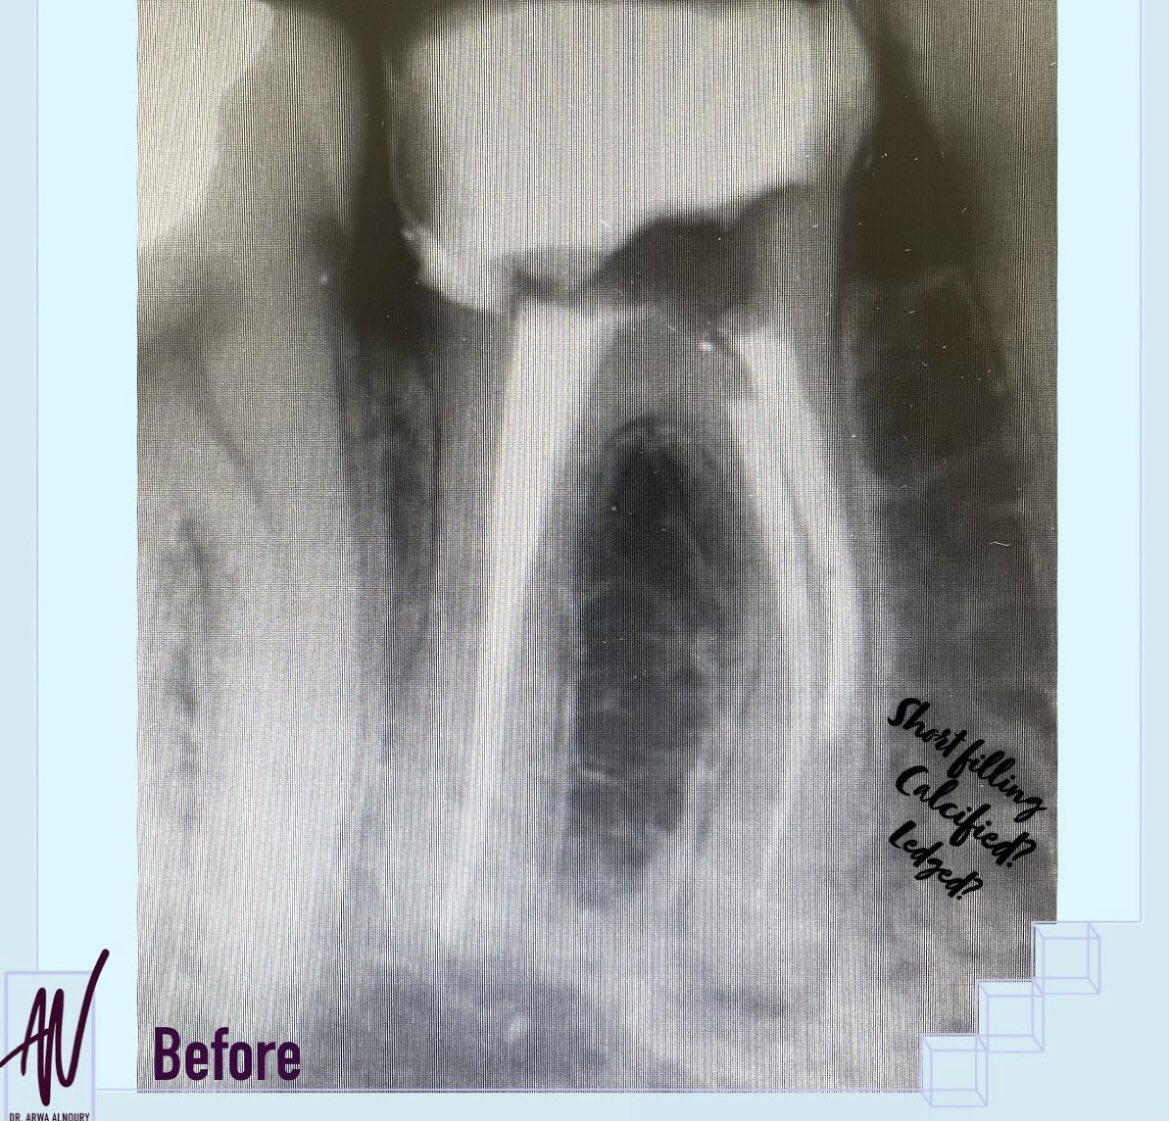

نعم هذه الصوره قبل وبعد ولكن..... شوفو معي خطوة بخطوة كيف قدرنا نحافظ على هذا السن🦷❤️